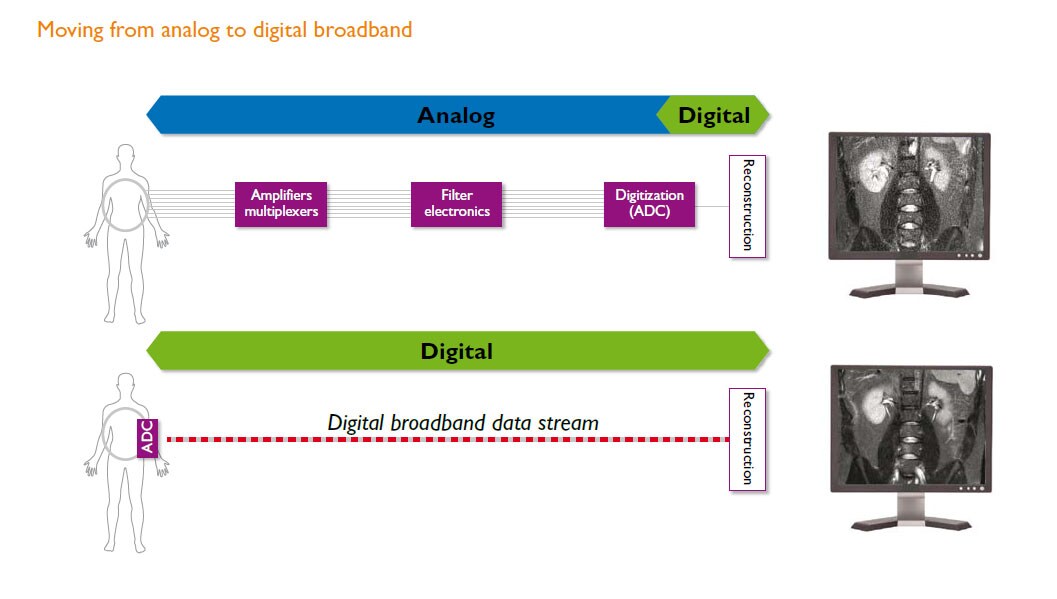

dStream technology, digital broadband architecture, digitizes the signal right in the coil.

High quality images and remarkable speed are possible with our dStream digital broadband architecture. Enjoy up to 40% more SNR* and enhanced throughput with channel-independent RF technology that makes upgrades easy. dStream digitizes the signal right in the coil, eliminating noise influences typical of analog pathways, to capture the MR signal without pre-distortion or compression. A fiber-optic connection from the coil to the image reconstructor enables lossless broadband data transmission.

The dStream architecture uses a DirectDigital RF sampling method for digitization: the MRI signal is sampled directly, without conversion to DC. This technique avoids all intermediate analog stages for down-conversion of the signal between the coil element and the analog to digital converter (ADC).

The overall result is a simplified receiving architecture, with few components, low power consumption, high SNR and dynamic range, and enhanced signal and phase stability.

Digitization takes place in the coil itself. ADC electronics have been miniaturized and placed within the coil.

One fiber-optic cable for any number of RF channels replaces multiple coaxial cables and retains image quality. The number of RF channels is no longer a system specification.